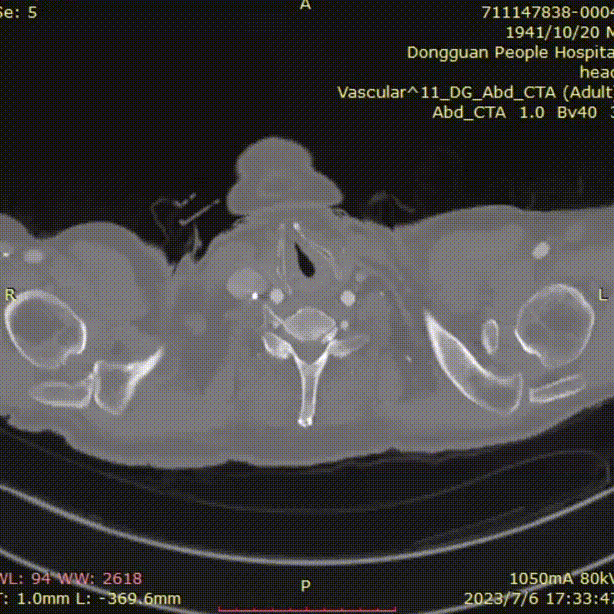

横断面影像

1)内膜多处撕裂,真腔严重狭窄。

2)CA假腔供血,SMA双腔供血,LRA假腔供血,RRA真腔供血,腹主段闭塞。

3)LSA起始部平均直径43mm+,降主段多发破口,真腔狭窄。